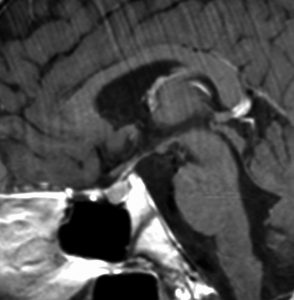

神経下垂体ジャーミノーマと大脳基底核成熟奇形腫

neurophypophyseal germinoma with basal ganglia mature teratoma

12歳の男児が尿崩症で発症しましたが,7ヶ月間診断がつかずに低ナトリウム血症による全身痙攣を生じました。下垂体と右被殻の2箇所に腫瘍があり,AFP 33ng/ml, HCG-beta 1.0mIUと上昇がみられました。神経下垂体の生検術でgerminomaの診断であったために化学療法が開始されました。CPA, VP-16, CDDP, VCRの併用化学療法に,MTXの髄腔内注入が2回でした。なぜこのような乱暴な化学療法を行なったのかは不明です。当然ですが,下垂体のgerminomaは左側のように消失しました。

でも化学療法中に,右大脳基底核にあった腫瘍が増大して,左のMRIのように脳浮腫も悪化しました。この時点で患者さんが転院してきました。腫瘍マーカーは陰転していて,どう見ても奇形腫が化学療法によるparadoxical responseを生じたものでした。ジャーミノーマが消えて奇形腫だけ増大するという現象です。

まず手術で全摘出して,成熟期奇形腫の病理診断を確定しました。それからICE化学療法を2コース加えて,脳脊髄照射 24Gy12分割を行いました。

大脳基底核に胚細胞腫瘍がある場合には全脳照射が基本ですが,なぜ脊髄照射を加えたかということには絶対の根拠はありません。治療前のAFPがやや高く若干の播種性格を有する未熟奇形腫が手術前に消失していたかもしれないという可能性を考えたことと,発症が12歳ですから脊髄照射を24グレイ加えても重篤な遅発性障害が生じないと判断したからです。